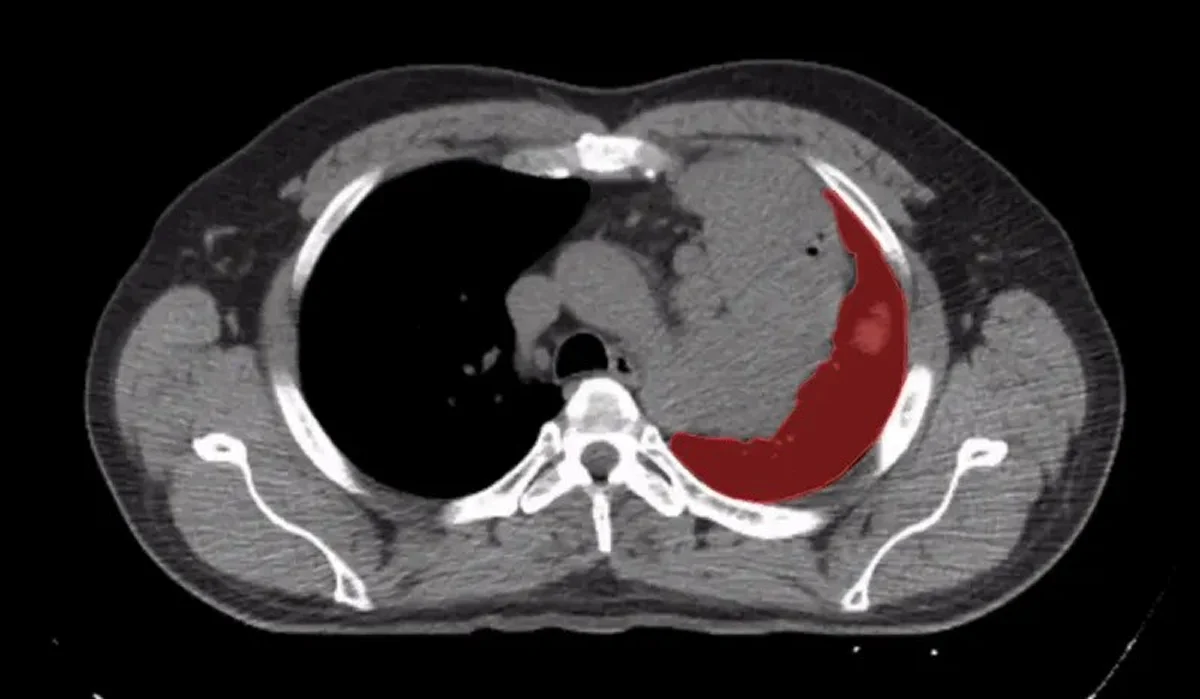

Pixel level segmentation implies that every pixel in an image is classified into a specific anatomical or pathological category.

In healthcare AI systems, even a few misclassified pixels can impact diagnosis accuracy. That is why pixel-level precision is now the gold standard in medical image annotation.

In oncology imaging, defining the exact boundary of a tumor determines treatment planning, radiation targeting, and surgical intervention.

Pixel level segmentation classifies every pixel in a medical image into specific anatomical or pathological categories, ensuring precise boundaries.